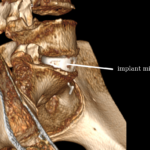

Implantacja implantu międzytrzonowego

- Duży cage ALIF (lordotyczny),

- Wypełniony:

- autograftem,

- allograftem,

- materiałem osteoindukcyjnym,

- Często:

- płytka przednia lub

- śruby kotwiczące w trzonach.